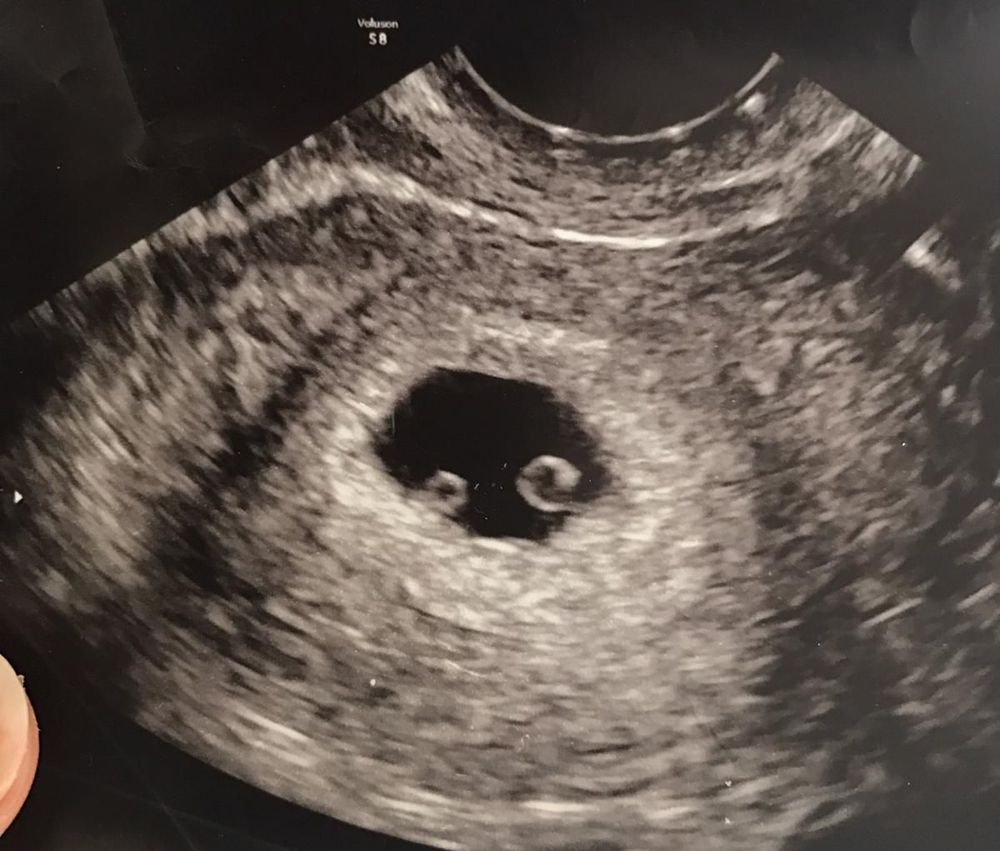

Smith was delighted to discover she was expecting twins in January 2017. These would be her first children with her fiancé, Richard Townsend.

But when her 12-week scan revealed that one of the babies had acrania, a rare congenital condition where the skull does not form properly, the prognosis was so grave that she made the heartbreaking decision to terminate the pregnancy.

The twins were identical and sharing a placenta, and so the couple were told by medics that, because one baby had acrania so severely, it was highly likely had the pregnancy continued, Sarah would have miscarried at a later date or given birth to two stillborn babies.